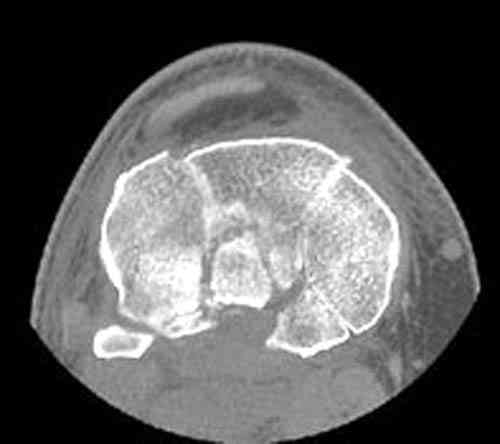

Based on the images ( it would be nice to have axial cuts),it seems to be posteromedial fragment, almost all the way into

posterior portion of the tibial eminance.

I thank for attaching the CT scan. it makes all the details very clear.

Для определения доступа сагитальные срезы менее информативны, необходимо иметь корональные срезы.

Корональные срезы дают информацию об апексе перелома, и также информацию о вовлечения суставной поверхности, что является немаловажным для прогноза.

Операция из разряда травматологической "экзотики" прошла успешно. Доступ понравился:анатомичный, хорошая визуализация, удобно работать и оператору и ассистентам. Наложили пневможгут, но воспользовались им только на этапе ревизии сустава. Фрагмент развернулся на 90 град. на 2-ух "жгутах": медиально - сухожилие m.semitendinosus, латерально - задняя крестообразная связка. Мобилизовали,развернули и уложили на место без особого труда. Фиксировали отмоделированной 1/3-трубчатой пластиной. Мениск оказался неповрежден. Сустав стабилен. Обошлись без

иммобилизации, планируем начать ранние движения. Остальное на фото, дополнительно приложены корональные срезы КТ.